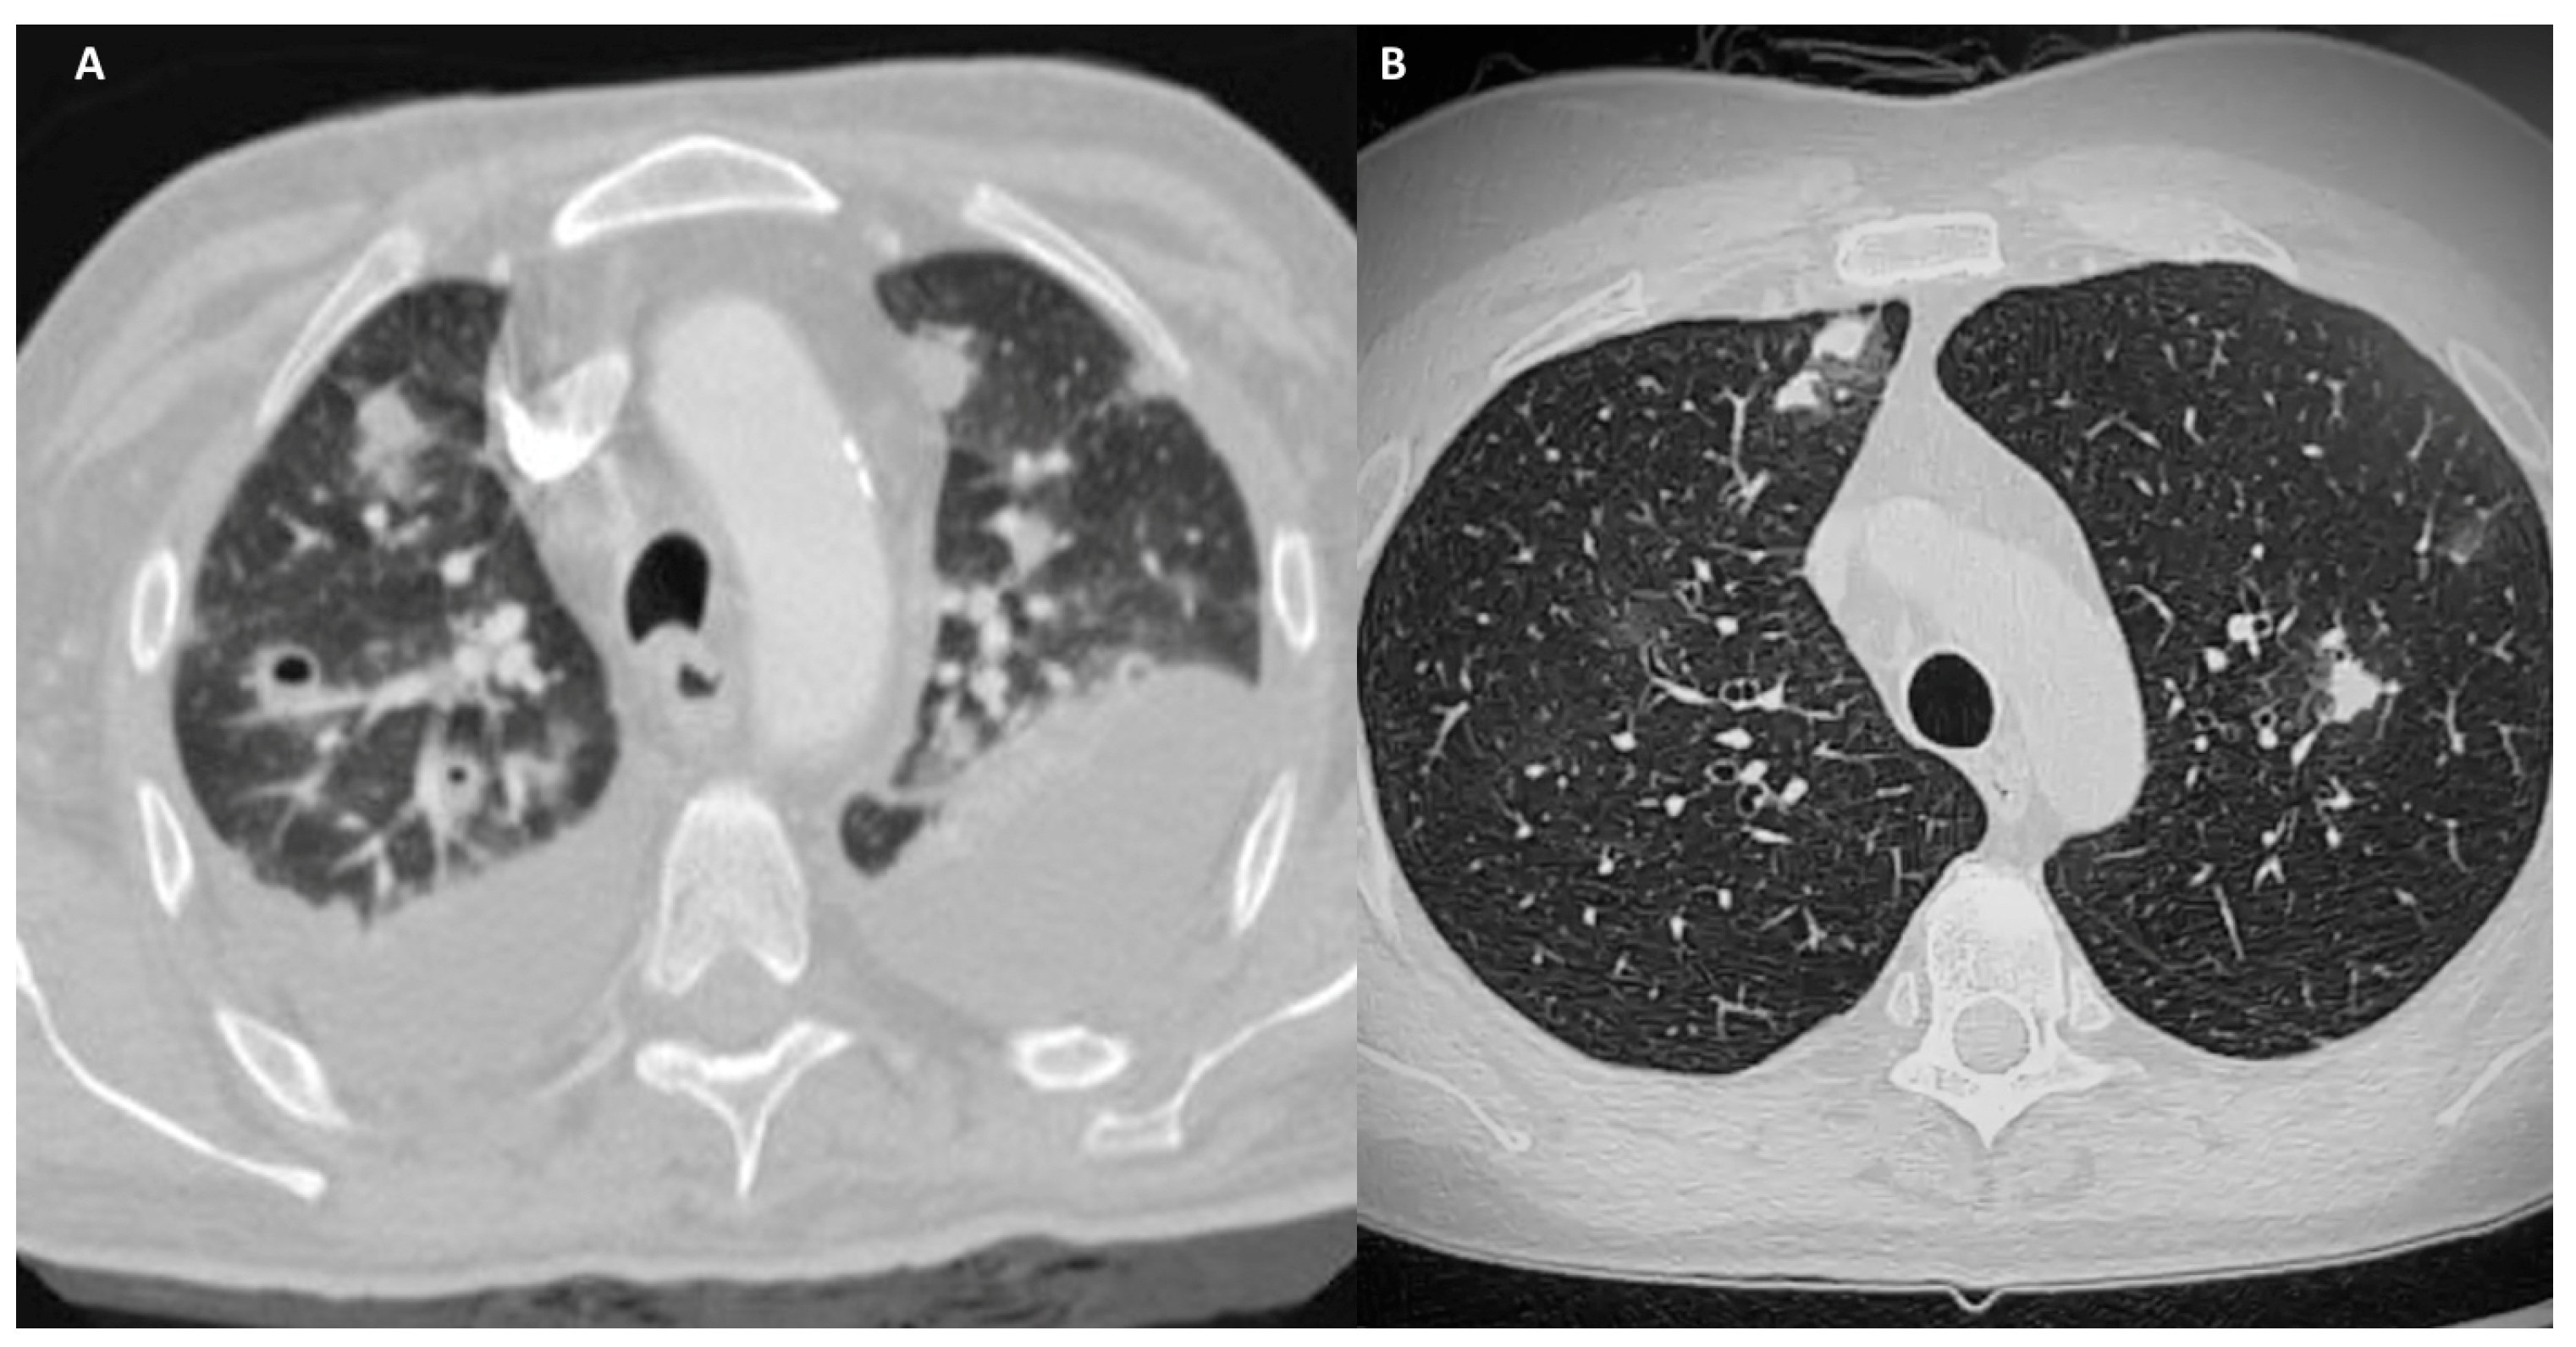

3. ANCA-Associated GLDs

3.1.4. Diagnosis

3.2.4. Diagnosis